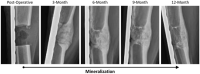

Bone tissue engineering is an emerging field of regenerative medicine, with a wide array of biomaterial technologies and therapeutics employed. However, it is difficult to objectively compare these various treatments during various stages of tissue response. Metabolomics is rapidly emerging as a powerful analytical tool to establish broad-spectrum metabolic signatures for a target biological system. Developing an effective biomarker panel for bone repair from small molecule data would provide an objective metric to readily assess the efficacy of novel therapeutics in relation to natural healing mechanisms. In this study we utilized a large segmental bone defect in goats to reflect trauma resulting in substantial volumetric bone loss. Characterization of the native repair capacity was then conducted over a period of 12 months through the combination of standard (radiography, computed tomography, histology, biomechanics) data and ultra-high-performance liquid chromatography-high resolution mass spectrometry (UHPLC-HRMS) metabolic profiling. Standard metrics demonstrated that samples formed soft callus structures that later mineralized. Small molecule profiles showed distinct temporal patterns associated with the bone tissue repair process. Specifically, increased lactate and amino acid levels at early time points indicated an environment conducive to osteoblast differentiation and extracellular matrix formation. Citrate and pyruvate abundances increased at later time points indicating increasing mineral content within the defect region. Taurine, shikimate, and pantothenate distribution profiles appeared to represent a shift toward a more homeostatic remodeling environment with the differentiation and activity of osteoclasts offsetting the earlier deposition phases of bone repair. The generation of a comprehensive metabolic reference portfolio offers a potent mechanism for examining novel biomaterials and can serve as guide for the development of new targeted therapeutics to improve the rate, magnitude, and quality of bone regeneration.